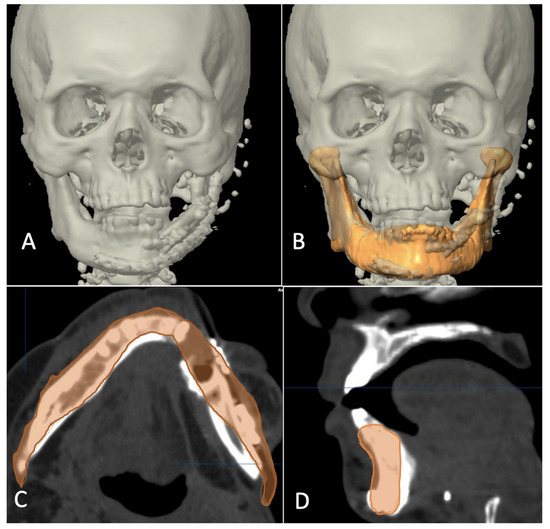

Figure 8.

Superimposition of planned and postoperative image in category I. (A) 3-dimensional view of outcome after reconstruction. (B) Superimposition of virtual plan (orange color) and post-operative data. (C) Axial view showing good match of reconstructed fibula to simulated mandible. (D) Sagittal view showing good match of reconstructed fibula to simulated mandible.